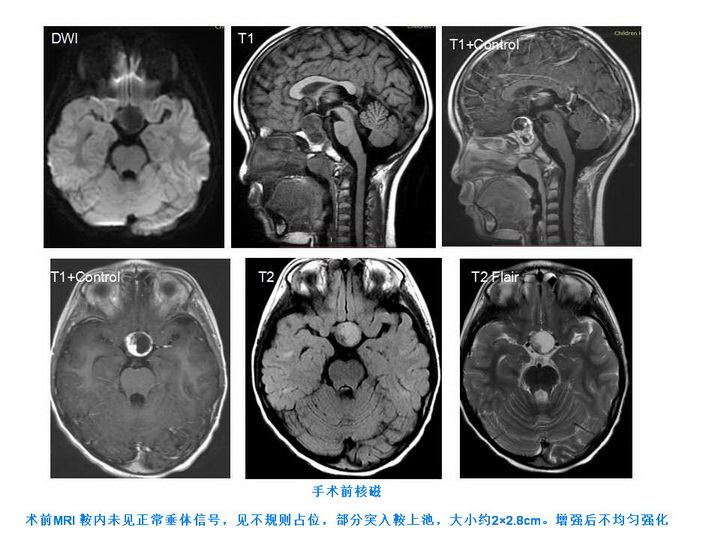

手术前核磁:

日前,首例神经内镜经鼻儿童颅咽管瘤切除术在复旦大学附属儿科医院神经外科成功完成。该例患儿为6岁男孩,因“发热、流鼻血”外院影像学检查,发现“鞍区占位”。转入我院后行头颅MRI检查,考虑“鞍区占位,垂体柄及视交叉受压”。肿瘤已明显压迫视交叉,必须尽快手术治疗。既往该病需开颅手术,但开颅手术需切开正常脑组织才能切除肿瘤,创伤大,手术风险大,术后并发症多,患者恢复慢。